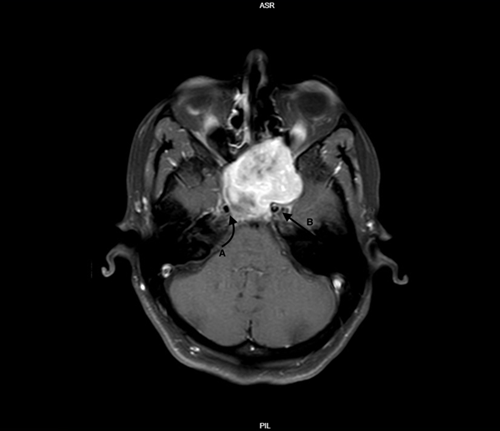

Figure 3: CT coronal view bone window showing bilateral vidian canals

Head and neck schwannomas are not uncommon. They most commonly arise from the vestibular nerve, acounting to around 51%7. Followed by the trigeminal nerve accounting for 8%7.  The diagnosis of schwannomas is typically made histologically. However, this could be predetected on preoperative imaging with certain charactarisitcs including iso or hypointensity on T1 images, hyperintensity on T2 images and enhancement with contrast.  The MRI scan is also helpful in determining the origin of these tumors with features such as bone remodeling and enlargement of ther bony canals of the affected nerve. Vidian nerve schwannomas are a rare entity with only previous 11 cases reported in the literature to our knowledge summarized in table 1(1-10).

Figure 3